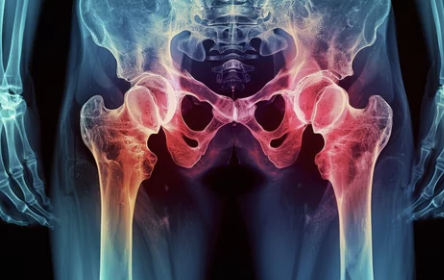

고관절 수술후 회복기간 알아보기

고관절 수술 후 회복, 희망찬 새 출발을 위한 완벽 가이드 💖

1️⃣ 고관절 수술 후 회복, 왜 중요할까요?

고관절 수술 후 회복 기간은 수술의 성공 여부를 좌우하는 중요한 시기입니다. 🤔 적절한 재활 운동과 관리를 통해 통증을 줄이고, 운동 범위를 회복하며, 합병증을 예방할 수 있습니다.

2️⃣ 고관절 수술 후 회복 기간은 얼마나 걸릴까요?

고관절 수술 후 회복 기간은 개인의 건강 상태, 수술 방법, 재활 노력 등에 따라 달라질 수 있습니다. 🤔 일반적으로는 다음과 같은 단계를 거치게 됩니다.